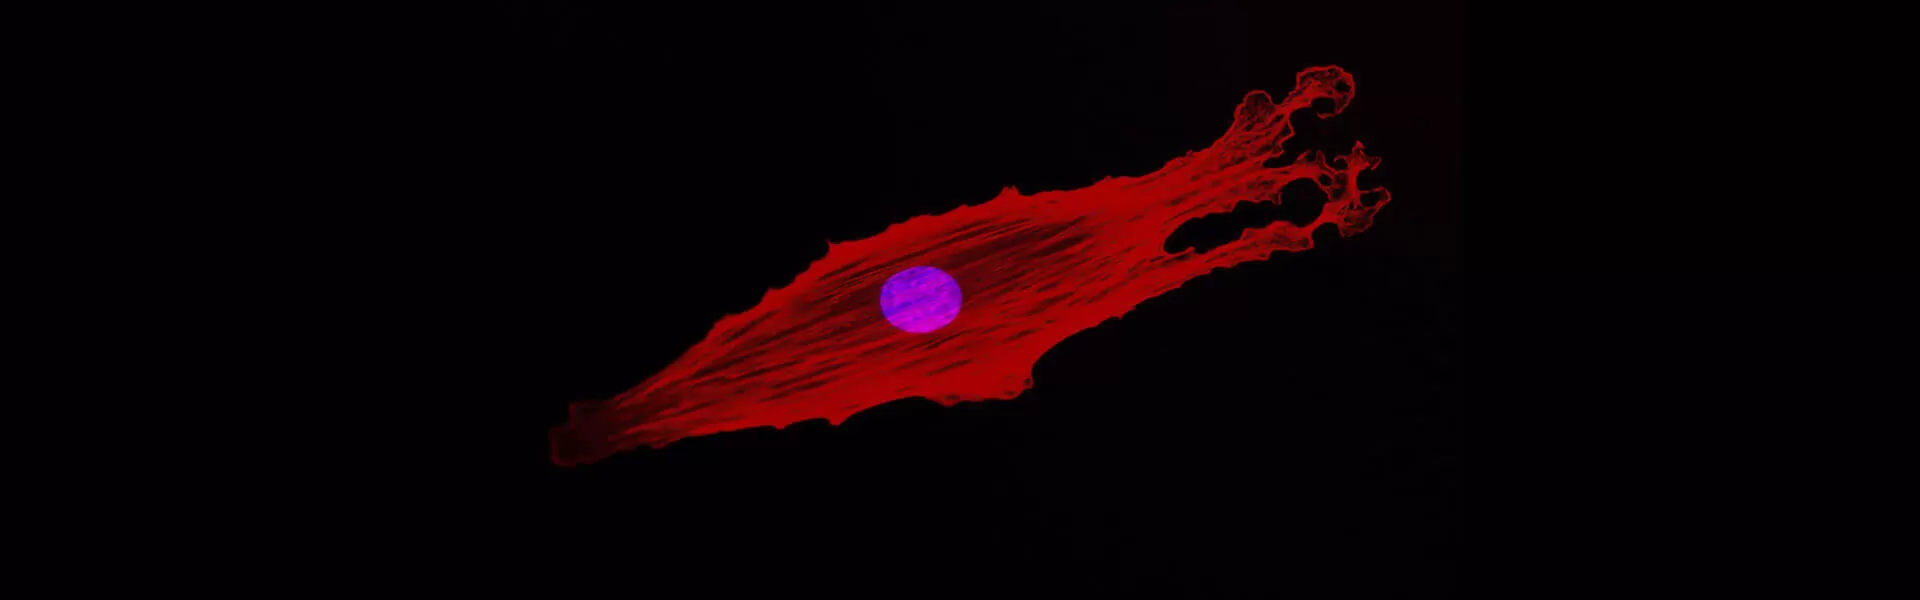

Exploring new ways to disarm rogue cells that have developed resistance is a major field of modern cancer research. One way to address the issue of resistance is to attack cancer through the fundamental processes that drive their core mission — to multiply unchecked and invade healthy organs.

Unlike traditional chemotherapy, which essentially poisons the cancer cells, medicines called cell-cycle kinase inhibitors put the brakes on uncontrolled cancer cell proliferation by blocking only key enzymes that drive cell division.

And using kinase inhibitors to mount a frontal assault on the machinery that drives cancer cell proliferation isn’t the end of the story. “While Pfizer does have an approved CDK inhibitor, cancers activate a different kinase to start growing again,” Dr. Dann says. When researchers discovered this was the case, they started working on strategies to address likely resistance.

“Tumor cells are always trying to find loopholes,” he says. “So, my work is focused on determining those mechanisms of resistance. We’re trying to figure out ways that the disease gets around that kinase inhibitor,” Dr. Dann says. “It's like having a half-filled balloon—you squeeze on one side and it just pops out the other. That's what's happening in a tumor cell. You're getting a lot of very quick evolution where those cells that survive tend to be more and more aggressive.”